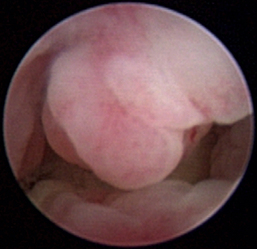

Normal turbinates have a smooth, pink-to-white surface and a spatial alignment that provides channels for the passage of air. The color varies and appears tan in the caudal nasal cavity. Turbinates come in different shapes and sizes, but the surface should be smooth. Ethmoid turbinates in the caudal nasal cavity will have a characteristic stippled or corrugated appearance (Figures 19-13 through 19-16). Ulcerations or various proliferations of the mucosa are indicative of disease. These changes are typically diffuse and accompanied by a lot of mucus. Mucus can be thin to purulent. Copious amounts can be flushed out of the nasal cavity to allow better visibility. The specific disease is determined by biopsy. After full examination of the nasal cavity, run the scope along the floor of the nasal sinus to the level of the choanae. Keeping the scope pointed in a ventral medial direction prevents inadvertent trauma or penetration of the cribriform plate. The index finger of the free hand can be used to follow the scope as it moves caudally over the hard palate; the surgeon can then palpate the scope through the soft palate when it moves into the nasopharynx. Some force is needed to complete this procedure and may result in increased bleeding.

image

Figure 19-13 Normal canine rostral nasal cavity; the septum is medial (left).